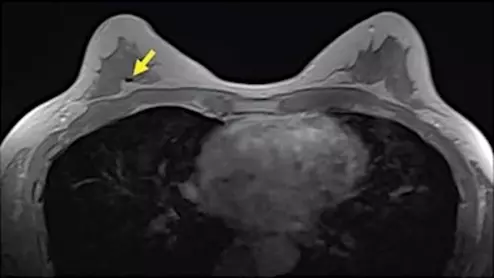

Breast MRI example showing a signal void in right breast (arrow) caused by biopsy on an axial contrast-enhanced in-phase Dixon image. It shows a signal void in right breast (arrow), which corresponded with a MammoMark/CorMark Bread Tie biopsy clip. Image courtesy of AJR.

A team of experts recently developed the new system to differentiate between malignant and benign "second look" lesions on MRI for women with known breast cancer.